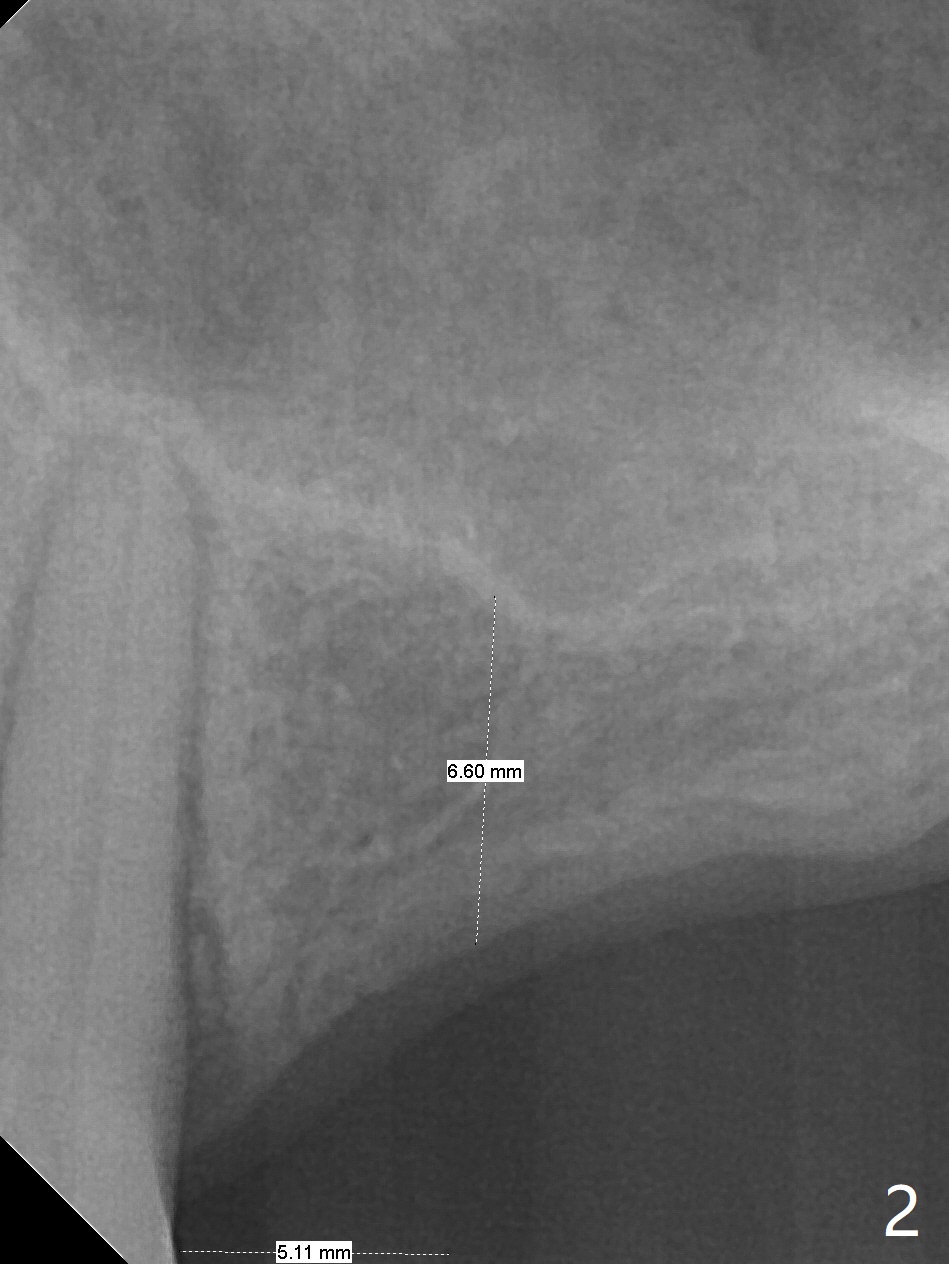

A 57-year-old woman has lost #14,15 and 18 for a while (Fig.1). Because of fear, an implant will be placed at #14 first (Fig.2). After use of Magic Drill for 5 mm (Fig.3), Magic Lifter will be used for lift (Fig.4). Following placement of PRF membrane (Fig.5 blue) and Vanilla Graft (red circles), a dummy implant is placed for additional lift (Fig.6 green). With placement of a larger and probably longer definitive implant, the graft may migrate distal due to gravity in sleep (Fig.7 arrow). In a few months, the bone height at #15 may increase to facilitate implant placement at #15.